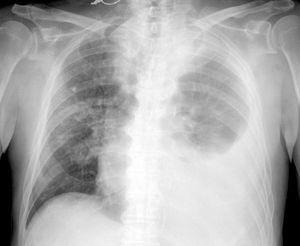

Acudió al Servicio de Urgencias por malestar general, anorexia y disnea progresiva de dos días de evolución. En la exploración destacaba saturación de O2 del 86% e hipoventilación de los dos tercios inferiores del pulmón izquierdo y tercio inferior del pulmón derecho. En la analítica presentaba 8.950 leucocitos/µl con 7,6% de eosinófilos, creatinina 3,1 mg/dl, sodio 126 mEq/l y gasometría venosa con pH 7,36, pCO2 26, PO2 31 y HCO3 15. Se realizó radiografía de tórax, en la que se observaba derrame pleural izquierdo masivo e infiltrado intersticial en pulmón derecho (fig. 1). Ingresó en el Servicio de Oncología procediéndose a toracocentesis evacuadora, de la que se obtuvieron 500 cc de líquido seroso compatible con trasudado. Dado el progresivo empeoramiento respiratorio se comentó el caso con nuestro Servicio, colocándose tubo endotorácico, sin mejoría clínica. Ingresó en la UCI, procediéndose a intubación orotraqueal y conexión a ventilación mecánica. Ante la posibilidad de toxicidad pulmonar por interleucina se suspendió el tratamiento inmunomodulador y se inició tratamiento corticoideo, con resolución completa del cuadro clínico y radiológico (fig. 2), pudiendo ser extubado en 48 horas sin complicaciones. El examen citológico y microbiológico del lavado broncoalveolar y del derrame pleural fueron negativos para malignidad y estériles, mostrando infiltrado inflamatorio de tipo mixto.

Figura 2. Resolución total del cuadro clínico y radiológico tras suspender el tratamiento inmunomodulador e iniciar tratamiento corticoideo.